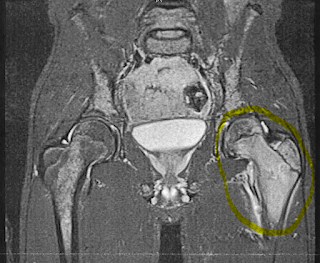

Logan is having a great day….currently he is over at a friends house getting some good x-box time in. His hip was feeling a little better this morning and he was able to lift his left leg slightly. Last night he had a little fever of just under 100. A little Advil and good nights rest cured that.

We are awaiting a call from Seattle Children’s Hospital on what’s next….initially when we met with his doctor last week she was going to call us give us our schedule once they had results back from the biopsy’s they performed. Kelly & I are planners but as anticipated our schedules right now will be determined by the amazing doctors at Seattle Children’s and faith.